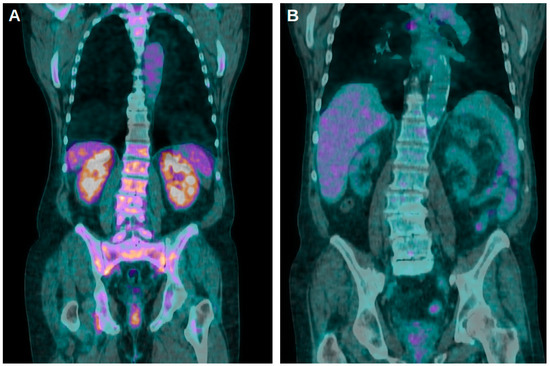

- Pijl, J.P.; Glaudemans, A.W.J.M.; Slart, R.H.J.A.; Kwee, T.C. 18F-FDG PET/CT in Autosomal Dominant Polycystic Kidney Disease Patients with Suspected Cyst Infection. J. Nucl. Med. 2018, 59, 1734–1741. [Google Scholar] [CrossRef] [PubMed]